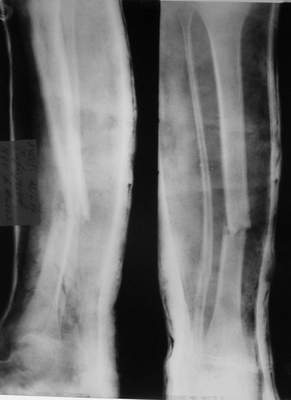

A> Перелом костей н\3 правой голени со смещением.

Это от 13.10.04? А это близкие к первичным снимки?

A> Перелом большеберцовой

A> кости можно охарактеризовать как компрессионно-оскольчатый.

Нормальный такой перелом... "шарнирный" я бы сказал... ну да есть

элемент сдавления (компрессии) по оси... и что?

а был у больного перелом дистального метафиза большеберцовой с чисто

варусным смещением на фоне пластической деформации малоберцовой на том

же уровне и того же характера.